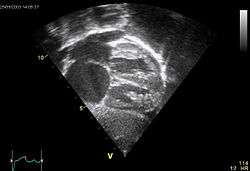

Echocardiography

In transthoracic echocardiography, an atrial septal defect may be seen on color flow imaging as a jet of blood from the left atrium to the right atrium.

If agitated saline is injected into a peripheral vein during echocardiography, small air bubbles can be seen on echocardiographic imaging. Bubbles traveling across an ASD may be seen either at rest or during a cough. (Bubbles only flow from right atrium to left atrium if the right atrial pressure is greater than left atrial). Because better visualization of the atria is achieved with transesophageal echocardiography, this test may be performed in individuals with a suspected ASD which is not visualized on transthoracic imaging. Newer techniques to visualize these defects involve intracardiac imaging with special catheters typically placed in the venous system and advanced to the level of the heart. This type of imaging is becoming more common and involves only mild sedation for the patient typically.

If the individual has adequate echocardiographic windows, use of the echocardiogram to measure the cardiac output of the left ventricle and the right ventricle independently is possible. In this way, the shunt fraction can be estimated using echocardiography.